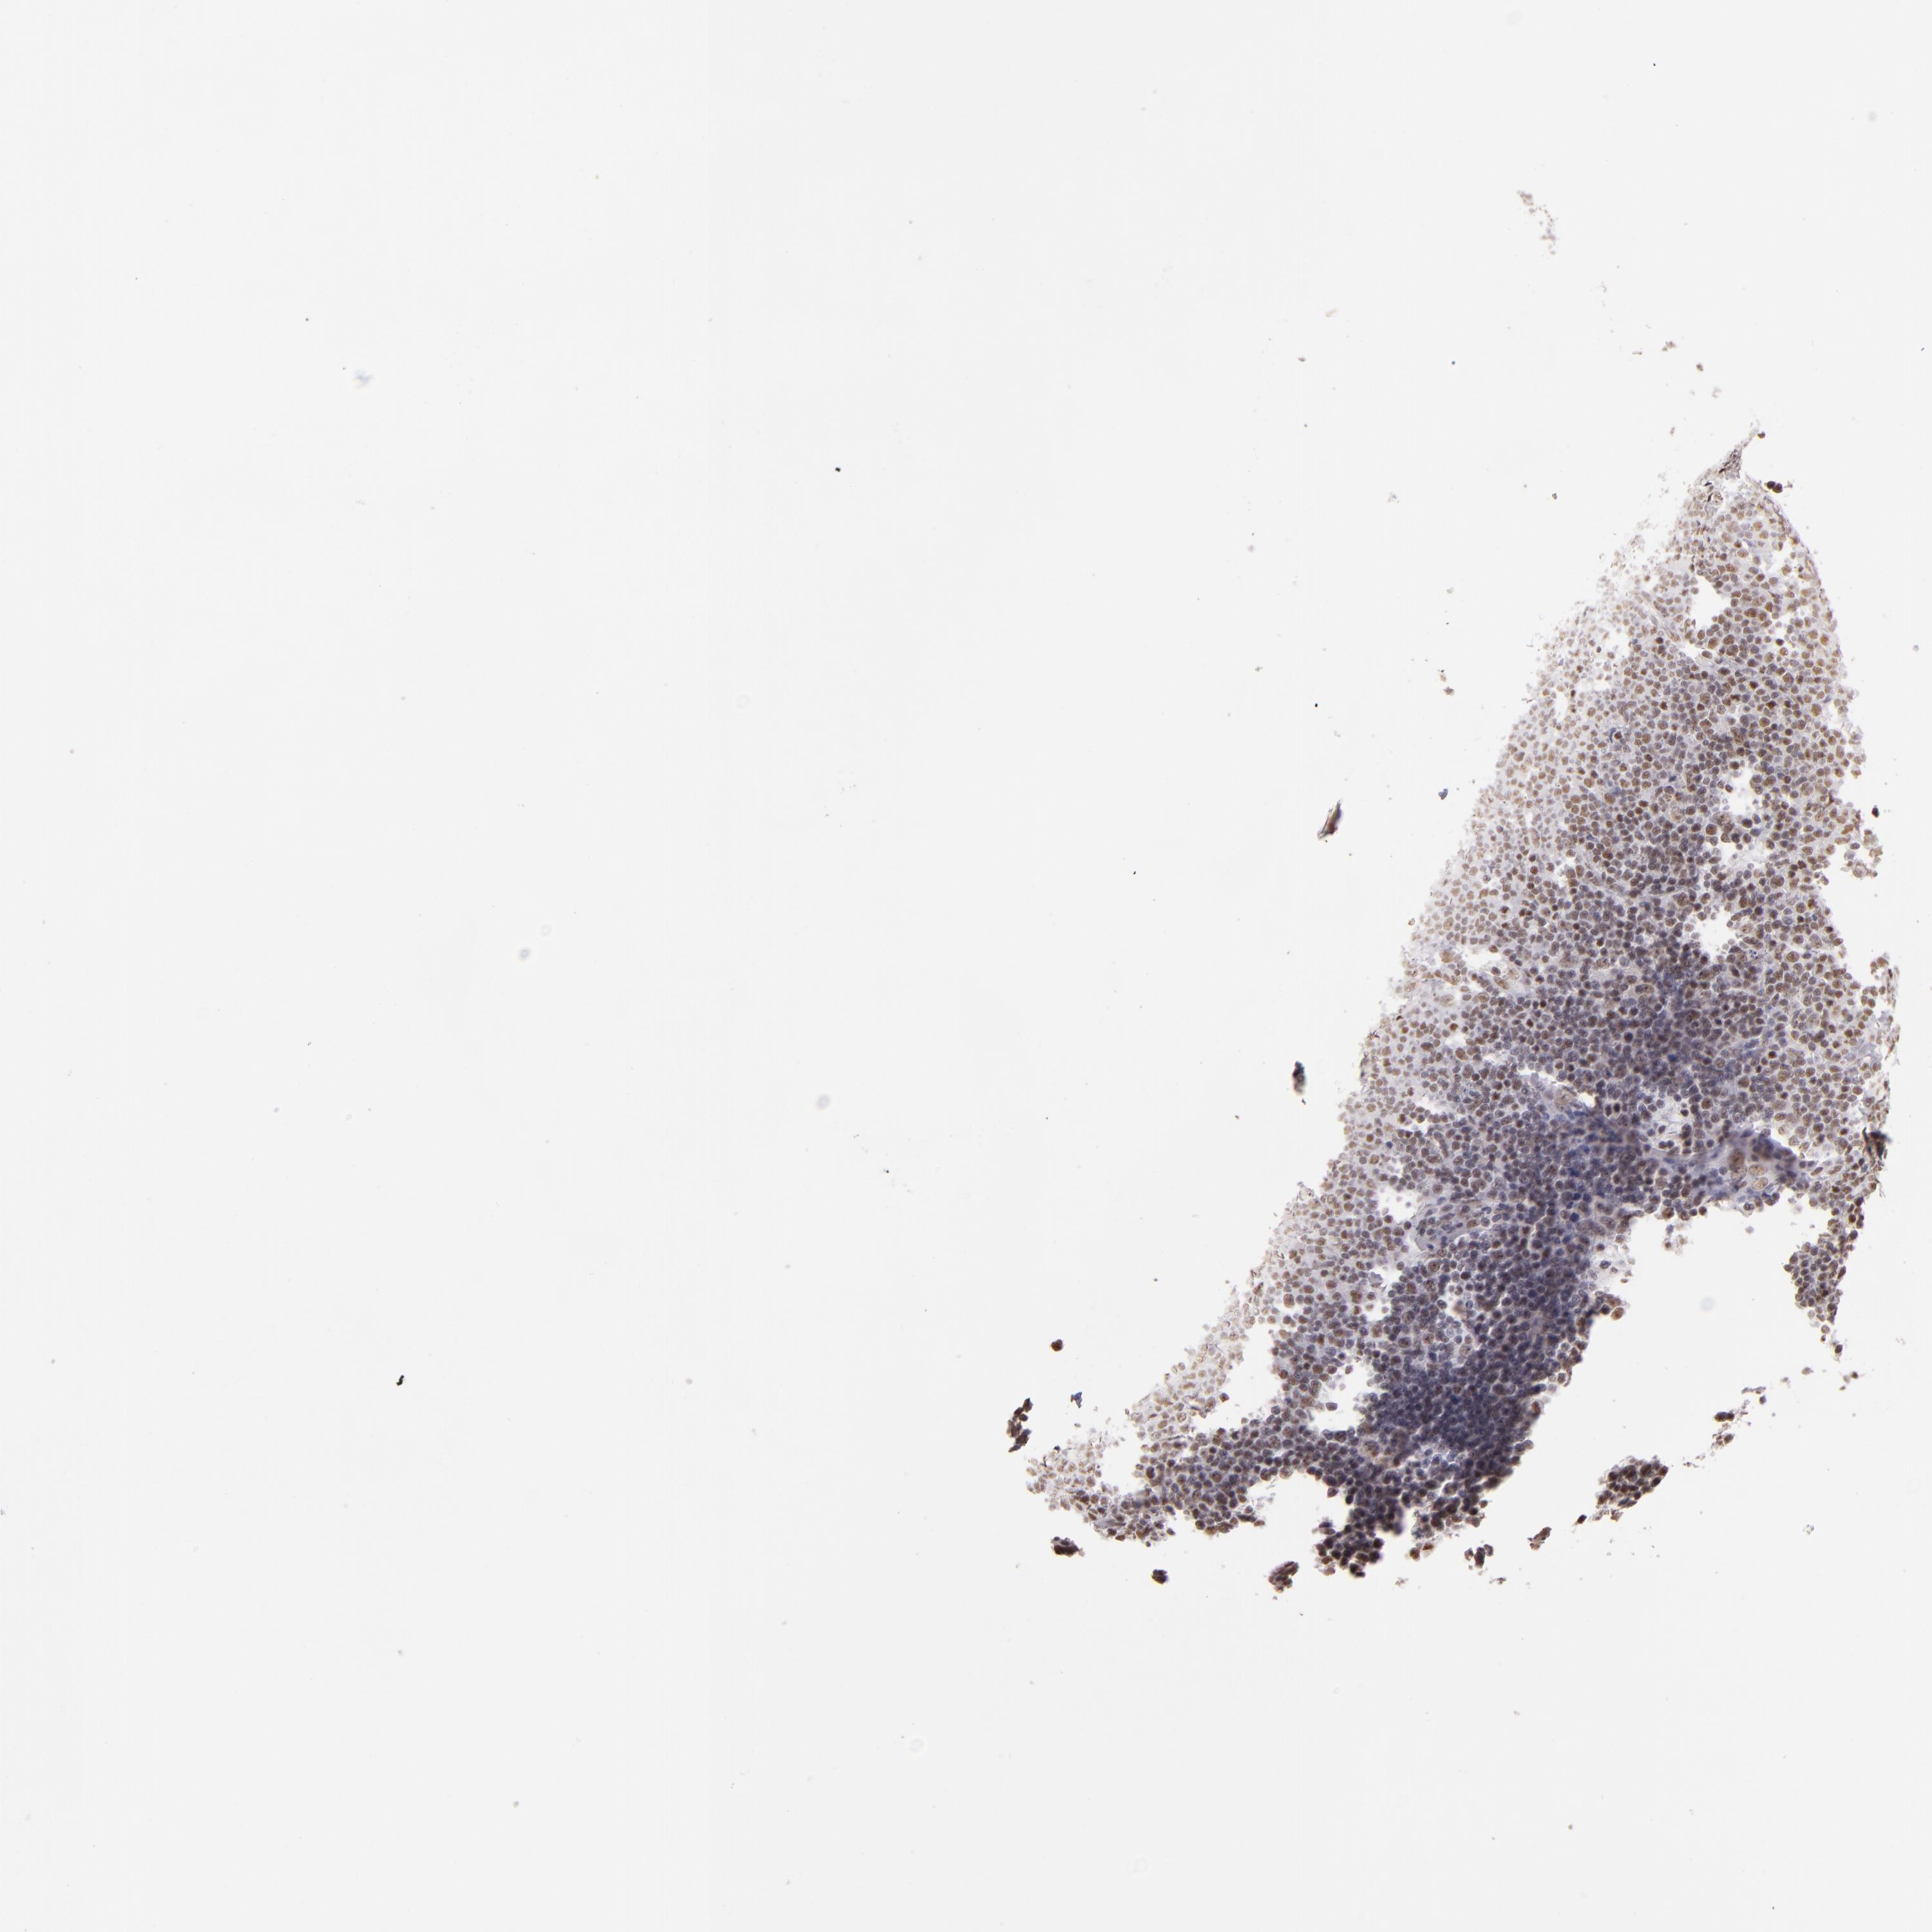

LYMPHOMA - Protein expressioni

A mouse-over function shows sample information and annotation data. Click on an image to view it in a full screen mode. Samples can be filtered based on level of antibody staining by selecting one or several of the following categories: high, medium, low and not detected. The assay and annotation is described here.

Antibody staining in the annotated cell types in the current human tissue is reported as not detected, low, medium, or high, based on conventional immunohistochemistry profiling in selected tissues. This score is based on the combination of the staining intensity and fraction of stained cells.

Each image is clickable and will lead to virtual microscopy that enables deeper exploration of all samples and also displays staining intensity scores, fraction scores and subcellular localization as well as patient and tissue information for each sample.

Antibody HPA001552

Antibody HPA001846

Staining

High

Medium

Low

Not detected

Intensity

Strong

Moderate

Weak

Negative

Quantity

>75%

75%-25%

<25%

None

Location

Nuclear

Cytoplasmic/membranous

Cytoplasmic/membranous,nuclear

Malignant lymphoma, non-Hodgkin's type, High grade

Malignant lymphoma, non-Hodgkin's type, Low grade

Hodgkin's disease, NOS